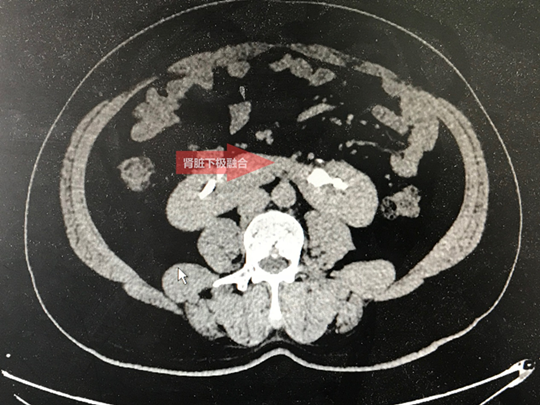

11月25日上午,我科收治了一位“马蹄肾”的患者。49岁的朱先生,沭阳七雄人,既往有肾结石病史,曾多次在外院碎石治疗,但治疗效果均不满意。因为腰部疼痛反复发作,朱先生感到痛苦不堪。患者入院后查CTU提示马蹄肾、左肾巨大结石。正是由于朱先生的马蹄肾、肾脏发育畸形,导致其在外院多次治疗均失败。

肾脏是人体的重要器官,普通人的肾脏有两个,左右两边各一个,并且相互独立。但是,有些人的两个肾脏是连在一起的,如字母“U”。这种病症,在医学上被称为“马蹄肾”。 马蹄肾是两侧肾脏的上极或下极相融合成马蹄,是一种先天性发育畸形。马蹄肾因肾脏旋转不全、肾血管多畸形、输尿管高植入、跨越峡部而受压,因此易引起肾积水、尿路结石及继发感染等,其中尿路结石最常见。

马蹄肾合并肾结石的治疗方法比较棘手。传统开放手术创伤太大,出血量较多,愈合时间延长。该患者U形肾畸形,但肾积水又很少,肾脏周边被腹腔脏器包绕,若行微创经皮肾镜取石术,术中可以穿刺的间隙很小,手术很容易引起肾血管和腹腔脏器损伤,对术者B超引导下穿刺技术要求非常高。手术风险极高,取石手术难度巨大。